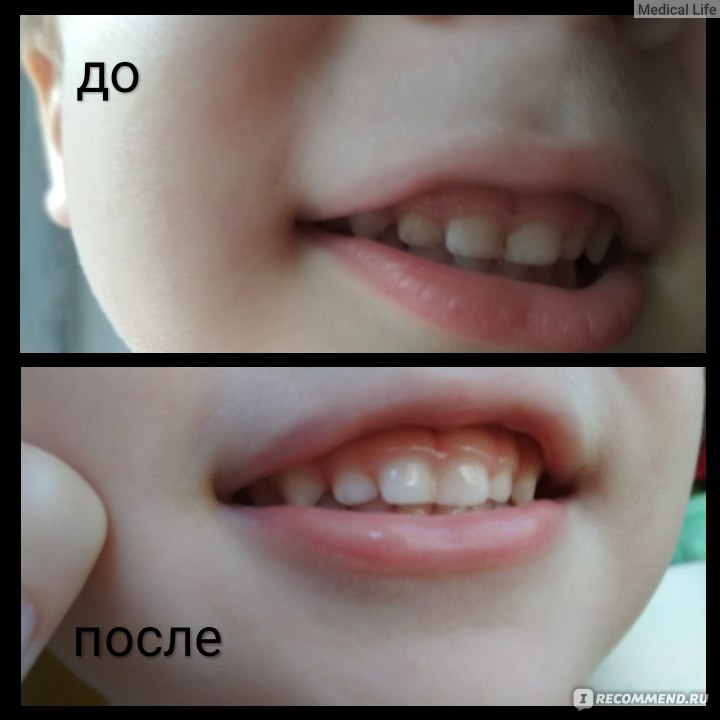

Иллюстрации флюороза молочных зубов

Раздел: Необычные решения